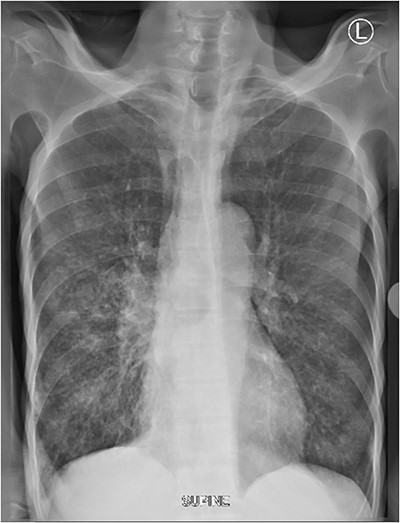

A 63-year-old male, 10-day post completion of anti-tuberculosis regimen for pulmonary tuberculosis, known smoker and alcoholic, presented with grade-5 dysphagia associated with food regurgitation, cough and weight loss. On general examination, he was ill looking, cachexic, dehydrated and pale, not jaundiced but no lower limb edema. His vitals were blood pressure of 139/71 mmHg, Temperature of 35.8°C, oxygen saturation of 95% on room air, respiratory rate of 18 cycles per minute and a pulse rate of 73 beats per minute. He had a scaphoid abdomen with tenderness on the right lumbar region. Fine crepitations were heard with reduced air entry on the right side of his chest. Full blood picture was done which was normal with a haemoglobin of 11.3 g/dl, other investigations including renal function tests and liver enzymes were normal. Chest X-ray done showed signs of metastasis (Fig. 8). CT-scan of the abdomen done at the referring hospital with both oral and intravenous contrast reported structures above the diaphragm showing dilated oesophagus measuring 41 × 38 mm due to distal retro-cardiac concentric oesophageal wall thickening amounting to 18 mm with luminal narrowing with possibility oesophageal fistula tract. The gastric cavity was normal without focal lesions. OGD revealed the oesophageal mucosa was hyperemic with a blocking mass at 29 cm from the upper incisors. The scope was able to pass beyond the lesion. The cardiac, fundus and body mucosa was atrophic. There were metaplastic changes at the antrum and pylorus. Multiple biopsies were taken. Histology results revealed oesophageal well differentiated invasive squamous cell carcinoma.

Supine chest X-ray shows patchy infiltrates in the right mid and lower zone with micronodular infiltrates. Micronodules seen in the left lower zones.